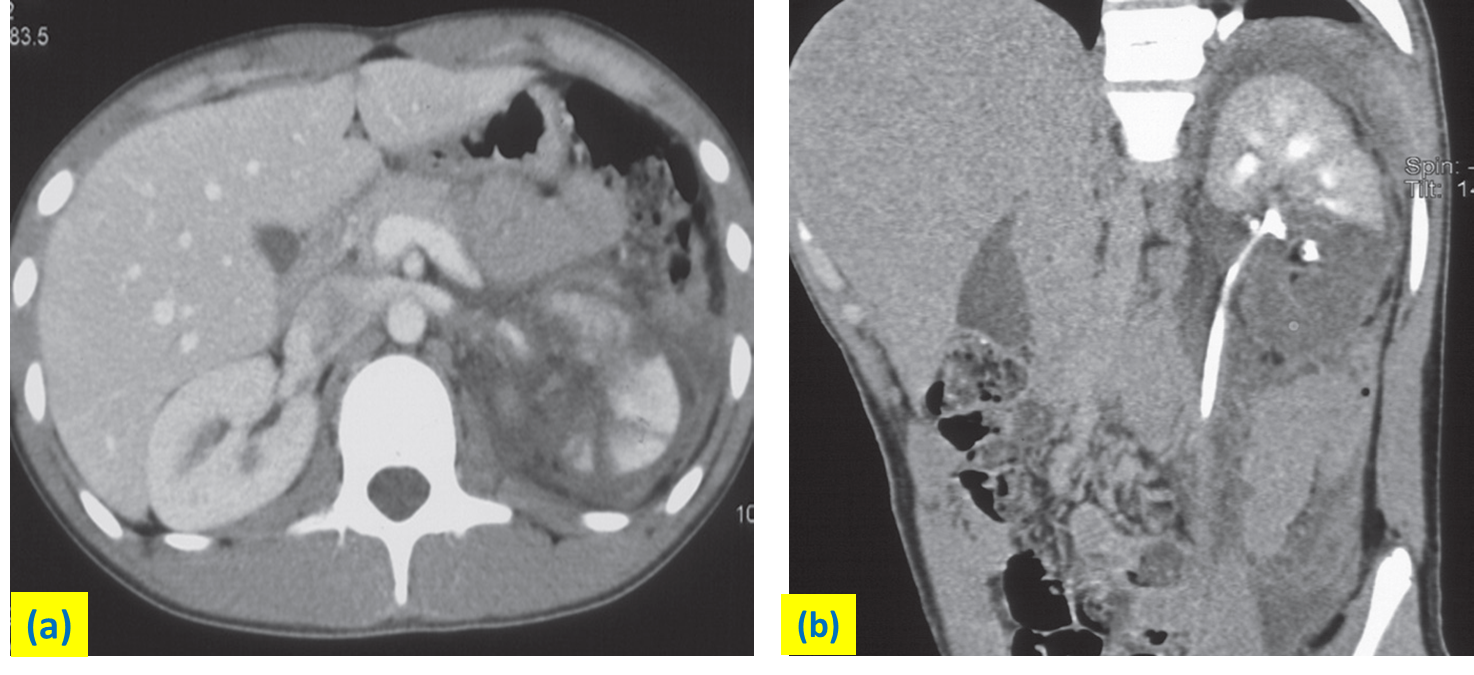

(a) Axial CT demonstrating reduced perfusion in the midpole of the left kidney. Fluid is seen in the perinephric tissues.

(b) Delayed oblique sagittal reformat demonstrating contrast in the collecting system and confirming no leak of contrast.